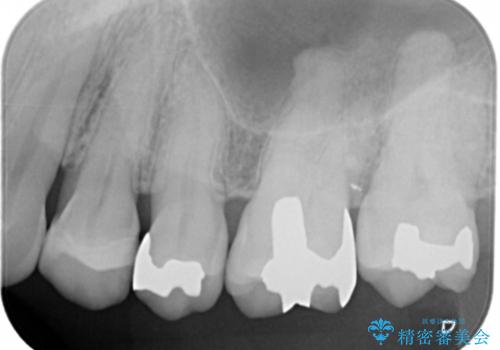

- 左上奥歯の銀歯のやり変えを希望された患者様です。

白くしたいとの事だったので形態・切削量を考慮し、セラミックインレーでの治療を計画しました。

保険材料と比較し、セラミックは劣化しない材料なので二次的な虫歯を防ぐことが出来ます。